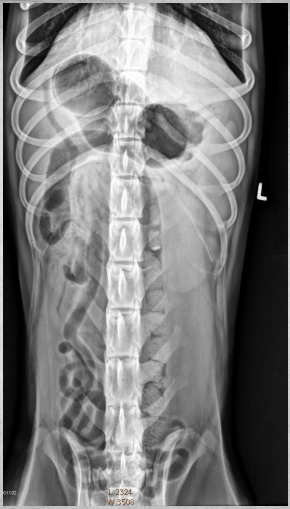

15 yo cat

Weight loss, anorexia, vomiting

Findings:

● Dilated bowel filled with fecal mass

– Not only large intestine, but small

intestine as well.

● Megacolon